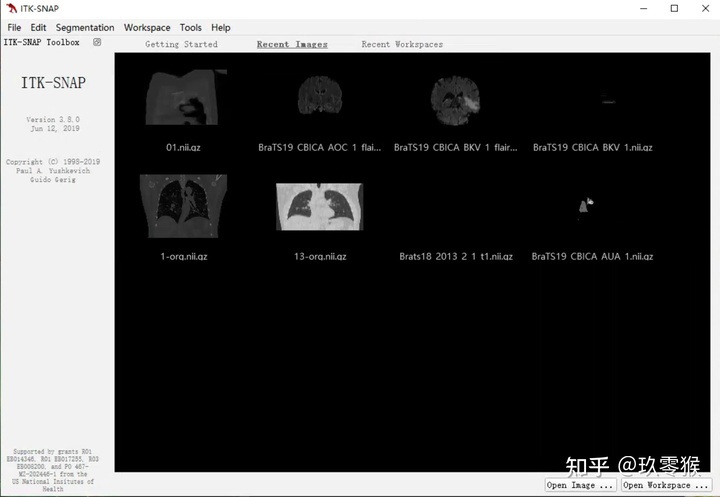

软件下载链接: ITK-SNAP Home

1、导入医学图像( nii.gz文件)

File->Open Main Image

点击 Browse... (切记不能有中文路径) -> Next